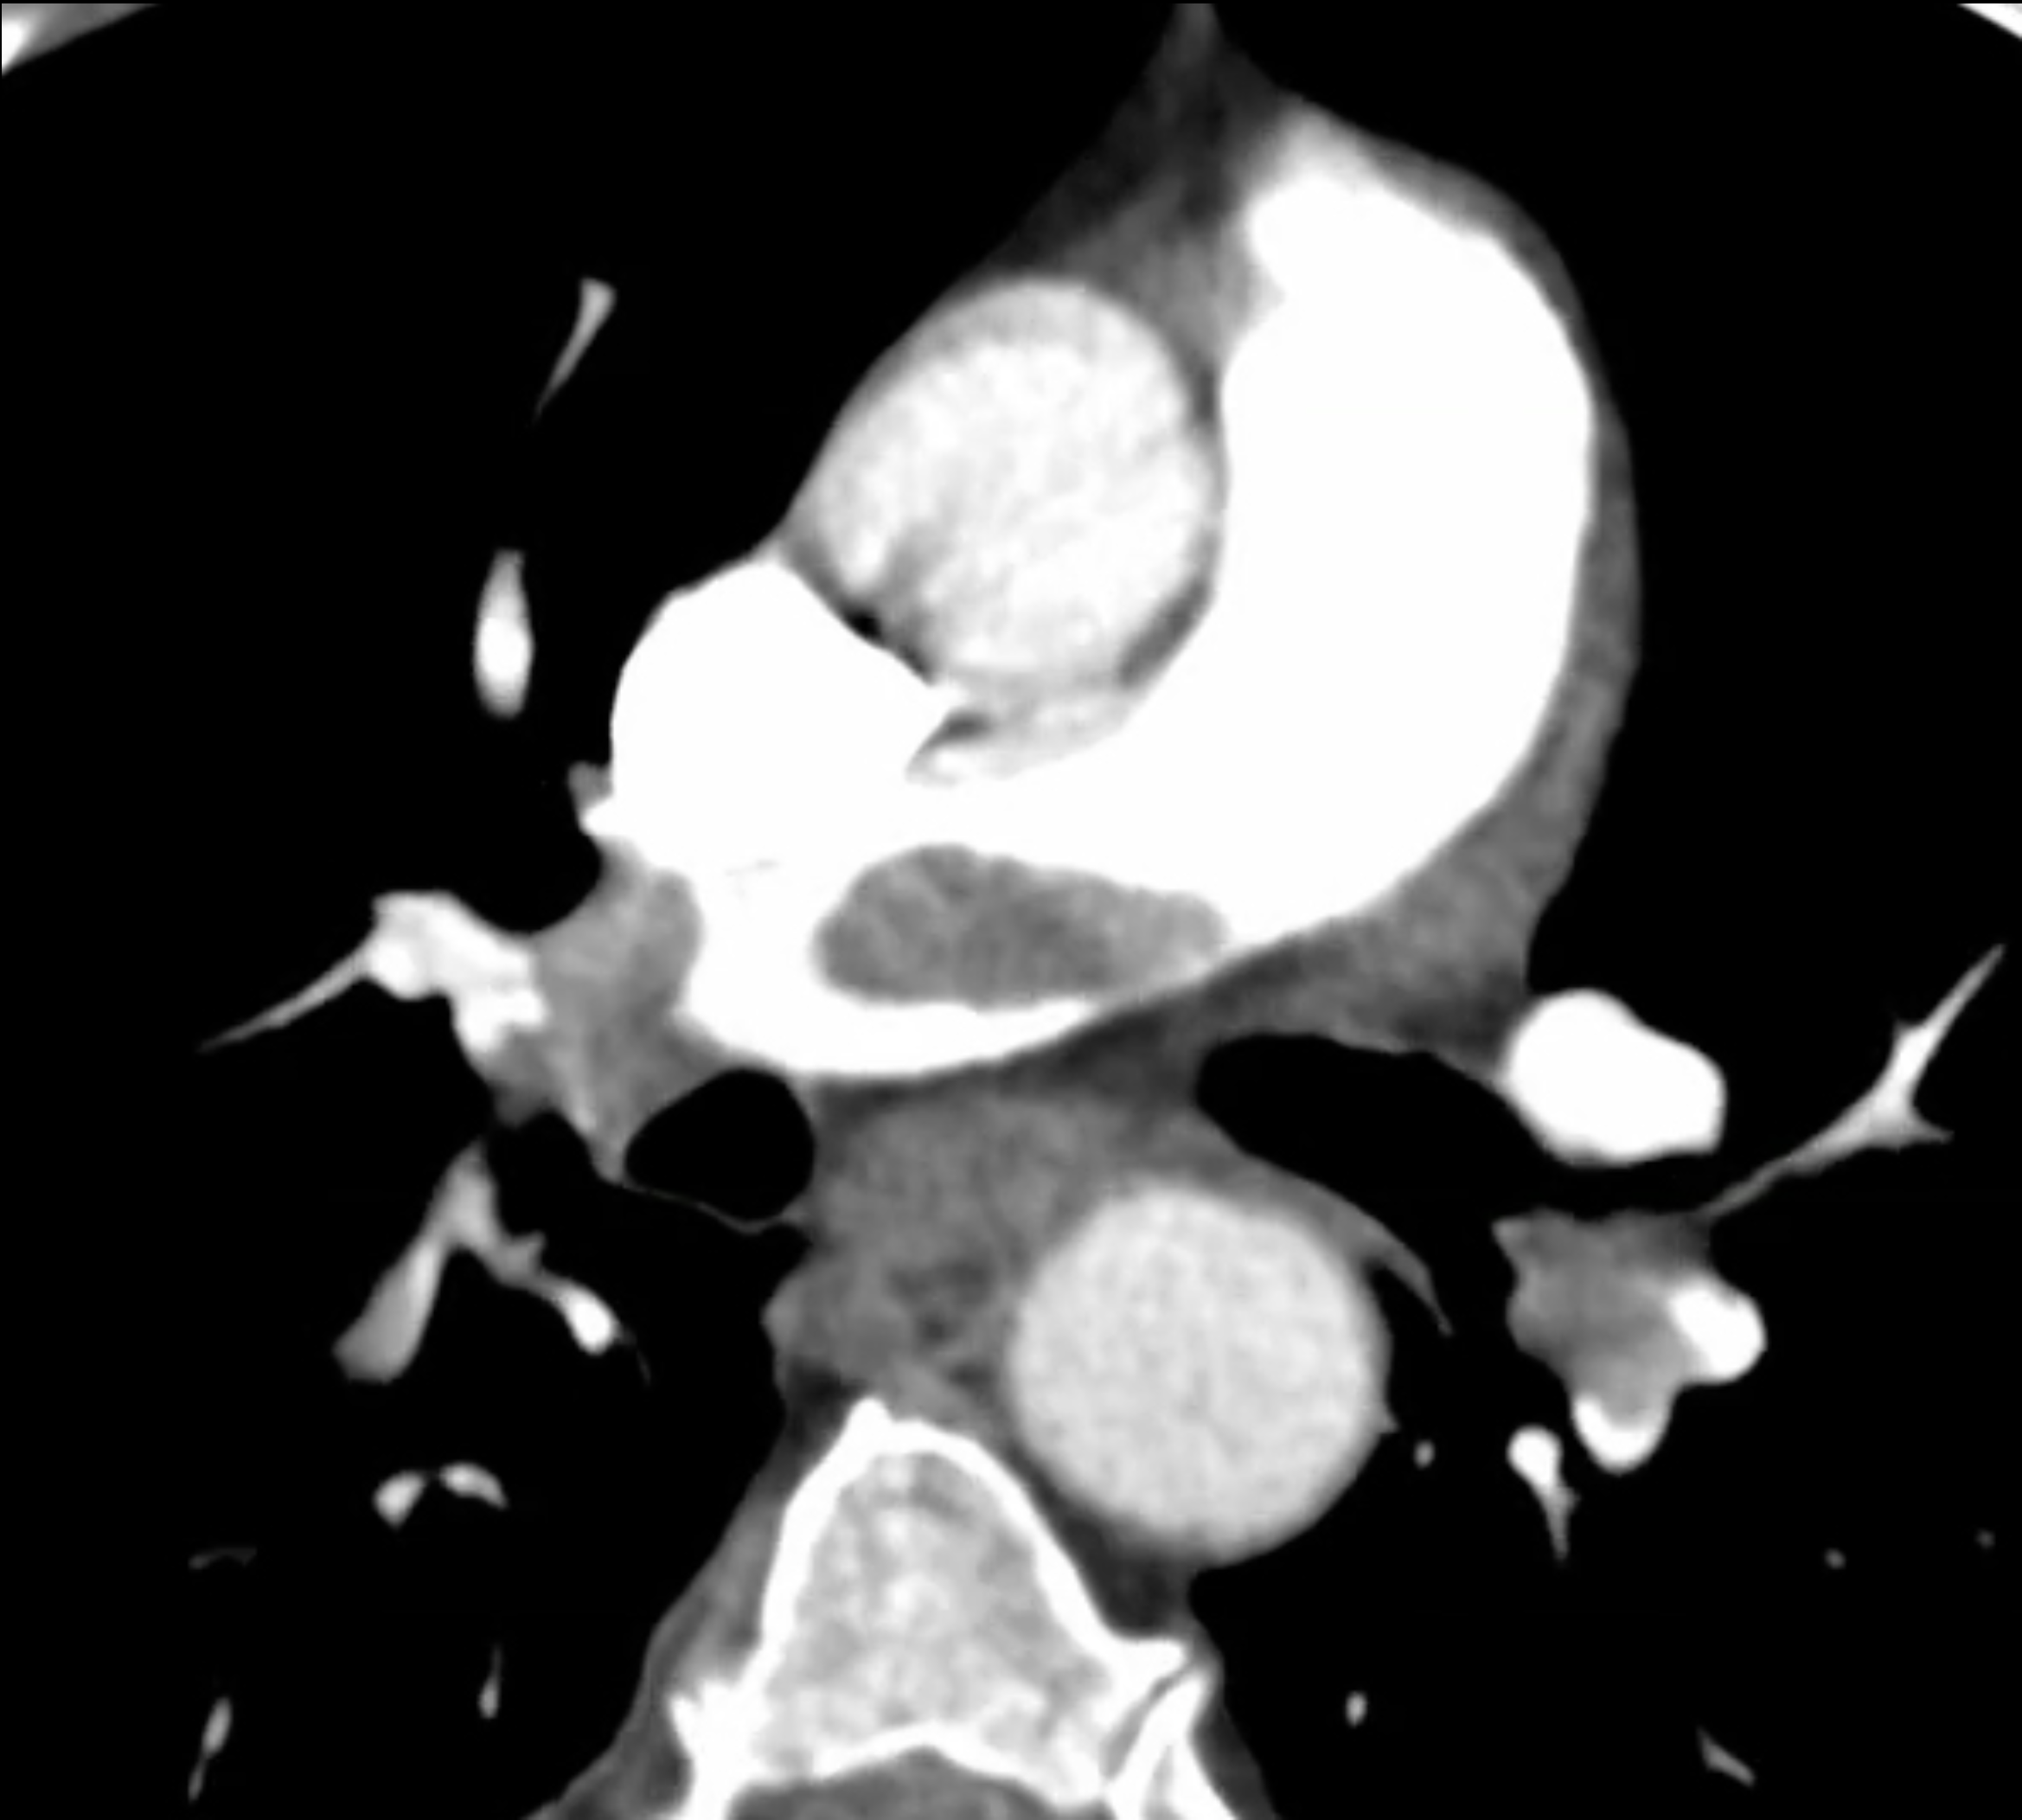

◂Chest CT for Internal Medicine Residents